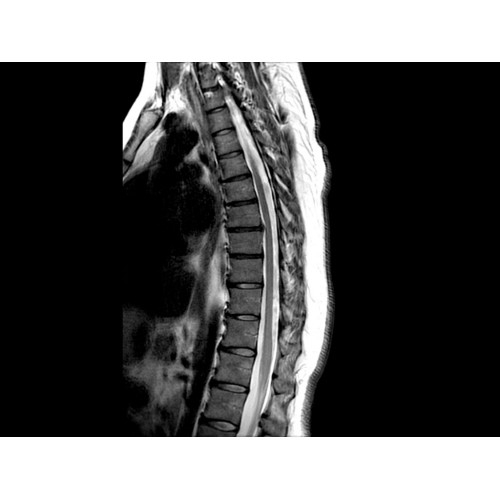

• Визуализация всего позвоночника слиянием двух участков — получить изображение всего позвоночника можно намного быстрее.